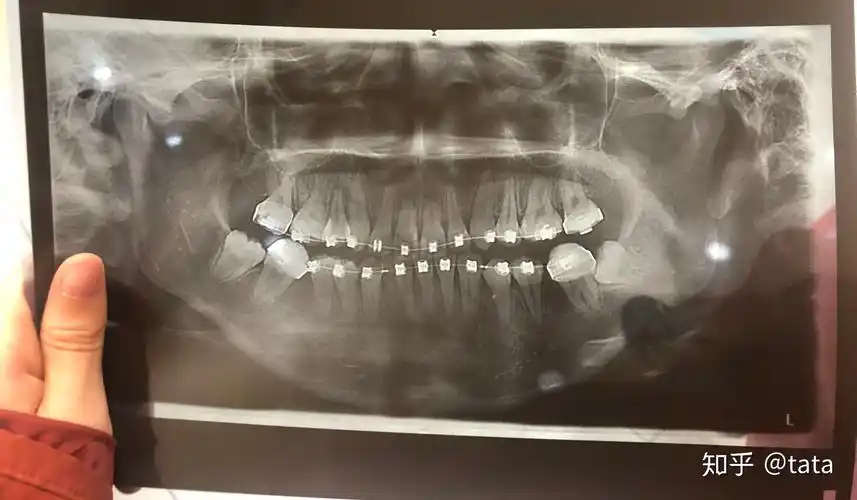

重度牙周病一定要拔牙么?牙槽骨严重吸收,还能种牙么?

牙槽骨吸收严重

这个牙槽骨吸收严重吗智齿可以用来牵引吗求大神解答

多牙松动,个别牙Ⅱ度松动, x线片显示:12,11,21,22,42牙槽骨吸收至根

这个牙槽骨吸收的严重吗?